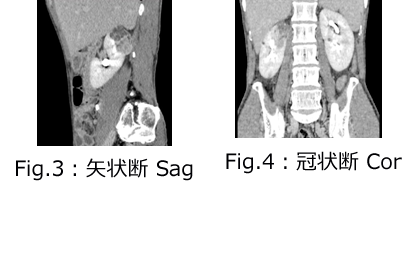

気軽に受診した結果、マルチスライスCTや心臓エコー・腹部エコーで重大な疾患が見つかることもあります。高血圧、糖尿病、脂質異常症の危険性を理解していただき、話し合いの上投薬を始めます。投薬開始後でも節制できた多くの方は内服を中止できています。長引く咳、風邪、AGA、骨粗しょう症、関節痛、足の浮腫み、頭痛、めまい、アトピー性皮膚炎、生理痛、物忘れ、不眠、不安、けが、予防接種など何科にかかればいいか迷う時は一度ご相談ください。「としだからしょうがない」とあきらめる前に一度ご相談ください。また、アレルギー治療には特に力を入れており舌下免疫療法では完治できている方が多数おられます。

放射線部門が担当するのは、①X線撮影(レントゲン)・X線透視 ②CT撮影 ③超音波検査です。